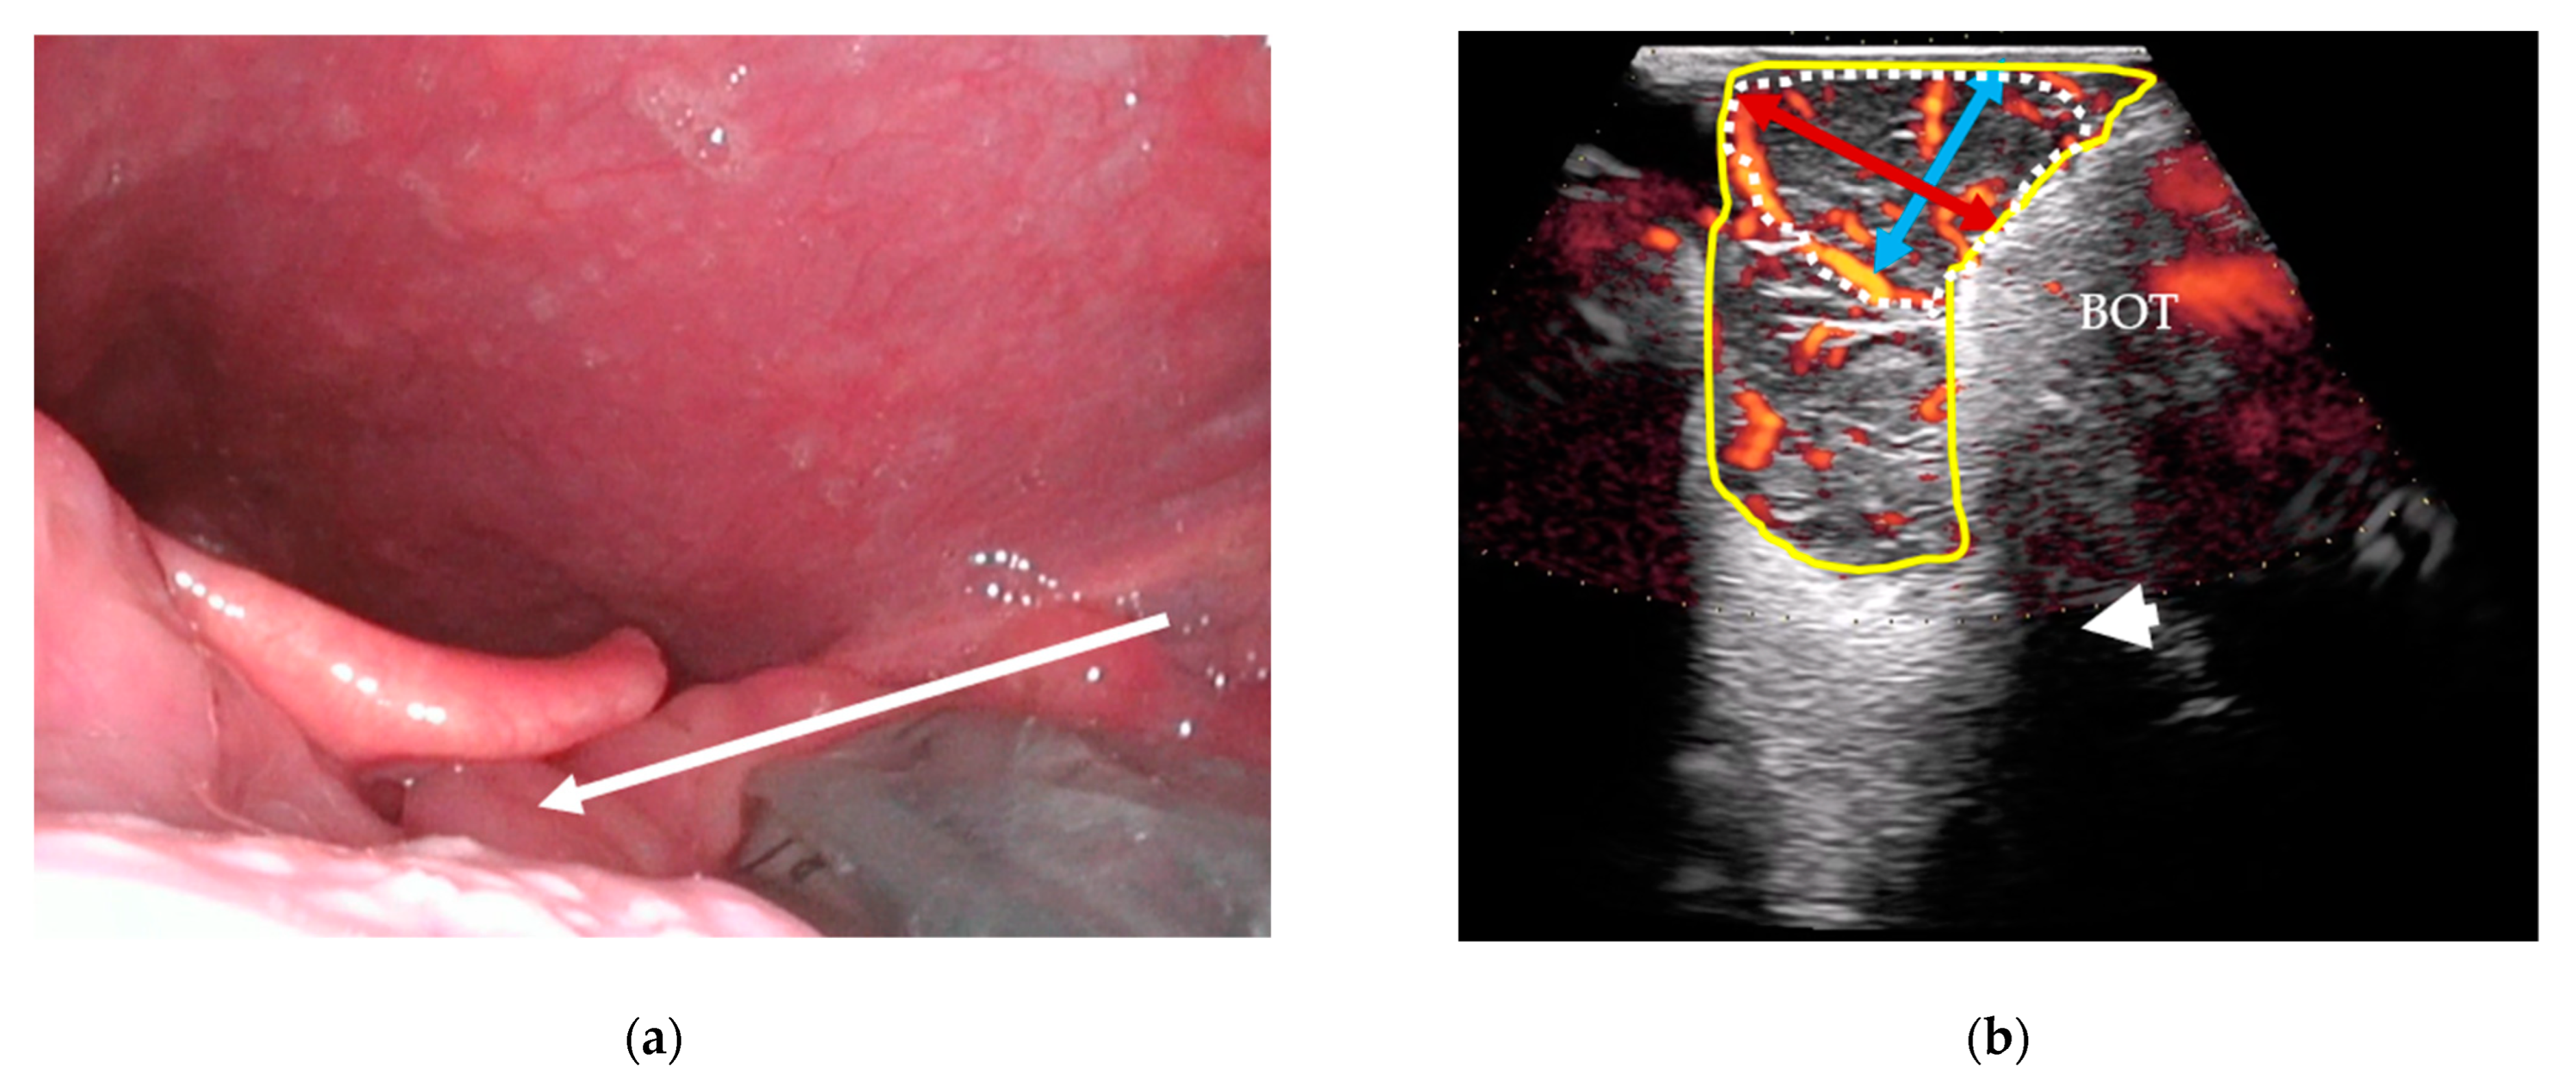

2.3.5. Outpatient-Performed Transcervical US

2.3.6. US Criteria for Tumor Detection

2.3.7. US Tumor Size Estimation and T-Staging